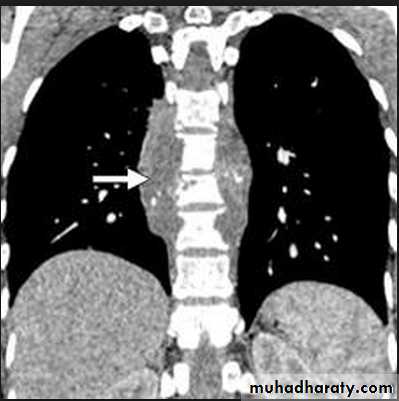

Massive pleural effusion with mediastinal shift to the left.

(A) Chest radiograph(B) CT coronal reconstruction. A massive effusion displaces the mediastinum to the left. CT shows the important pleural effusion together with the enhanced atelectatic left lung.

Note also the depression of the right hemidiaphragm (arrows).